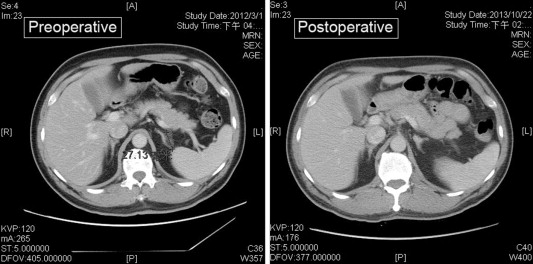

Pathological examination revealed that all adrenal tumors were removed en bloc ( Figure 1 ;  Figure 2). No peri- or postoperative complications occurred. All patients started oral intake and ambulation on the day of the operation. The early cosmetic results were excellent. The hospital stay was 1–6 days (mean, 3 days). None of the patients experienced tumor recurrence during the follow-up period. Fig. 3 shows a representative pre- and postoperative computed tomography of a single patient.

A right-sided adrenal tumor in a patient with an aldosterone-producing adenoma ...

Figure 1.

A right-sided adrenal tumor in a patient with an aldosterone-producing adenoma (prior to tumor resection). The green line indicates the margin of the adrenal gland and the broken line delineates the margin of the adrenal tumor.